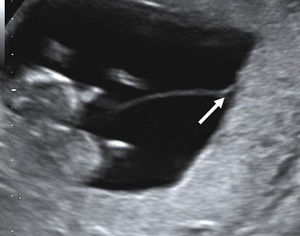

The visualization of a single chorionic sac at 4–5 weeks, however, does not exclude the possibility of a monochorionic twin pregnancy. By the sixth postmenstrual week the yolk sac and the embryo can be visualized inside the chorionic sac and the definitive diagnosis of a single pregnancy or monochorionic twin pregnancy can be done. If a single chorionic sac is visualized containing two yolk sacs and two embryonic poles, then a monochorionic twin pregnancy can be diagnosed (Fig. 2).